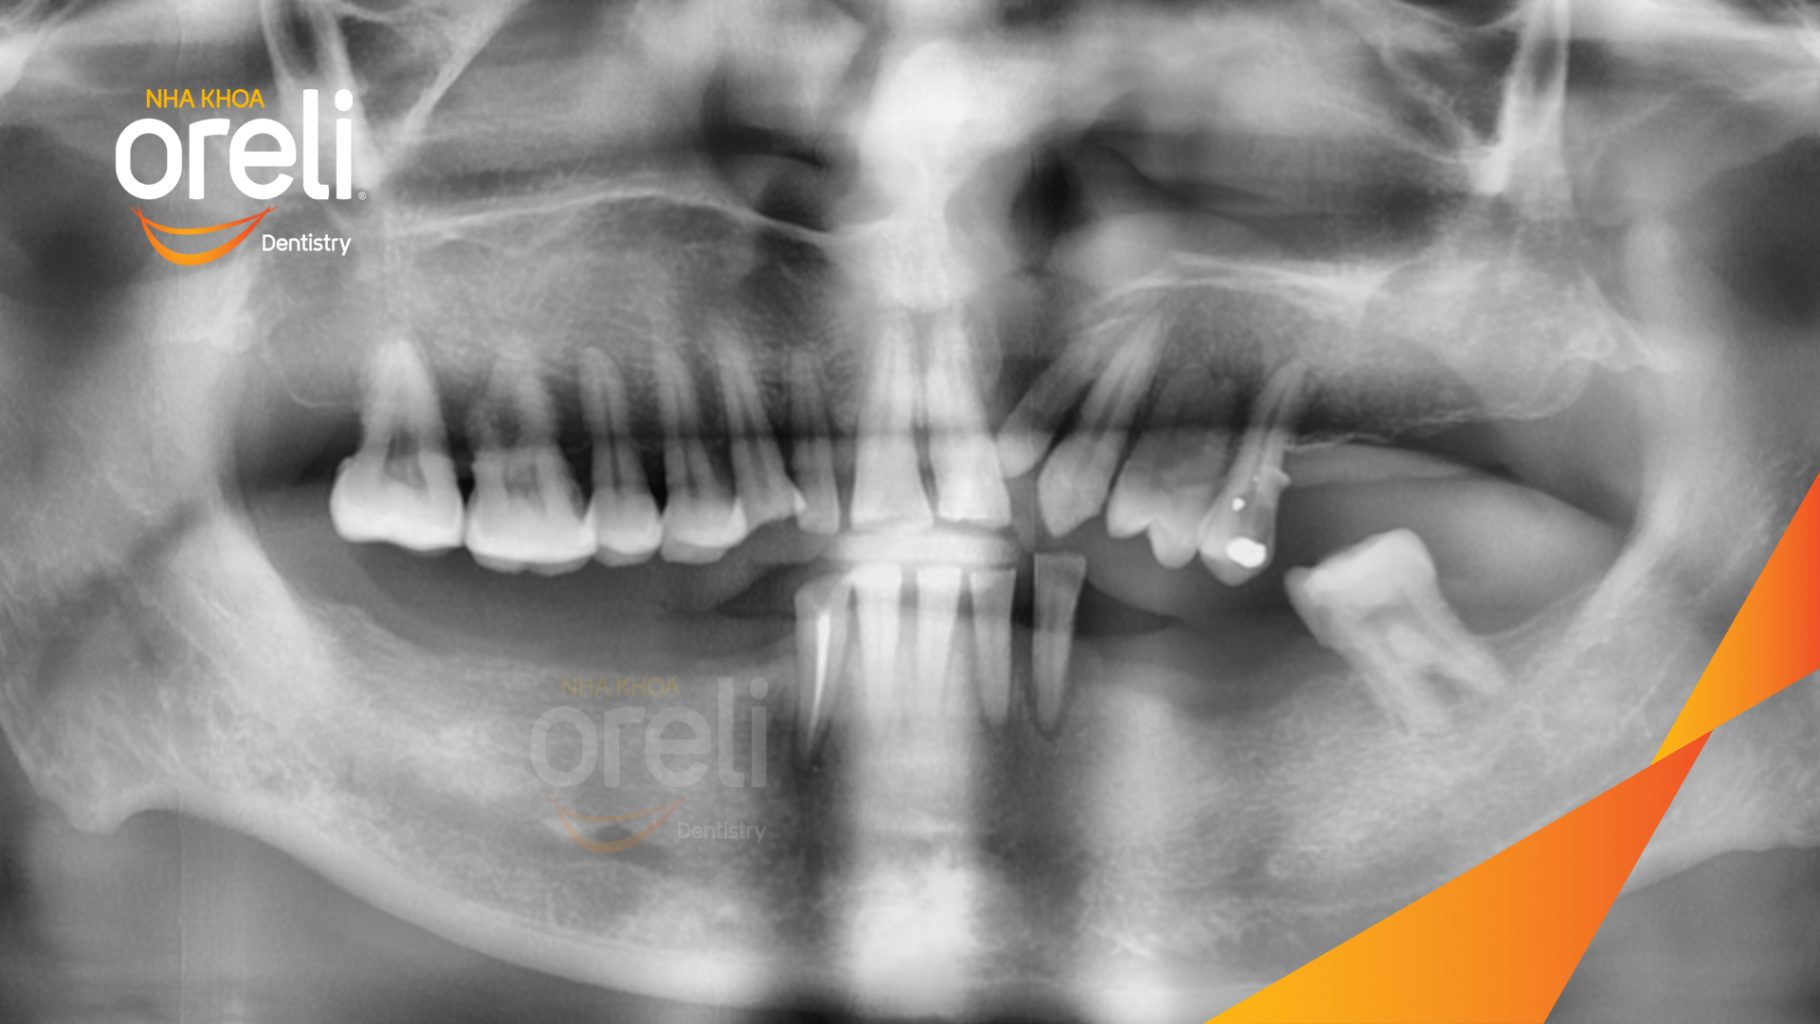

Tình trạng: Mất răng vùng răng sau hàm dưới, các răng trước lung lay mất khả năng hồi phục

Giải pháp: Nhổ răng trồng răng implant hàm dưới và hai răng hàm trên

Kết quả: Phục hồi vững chắc hàm dưới